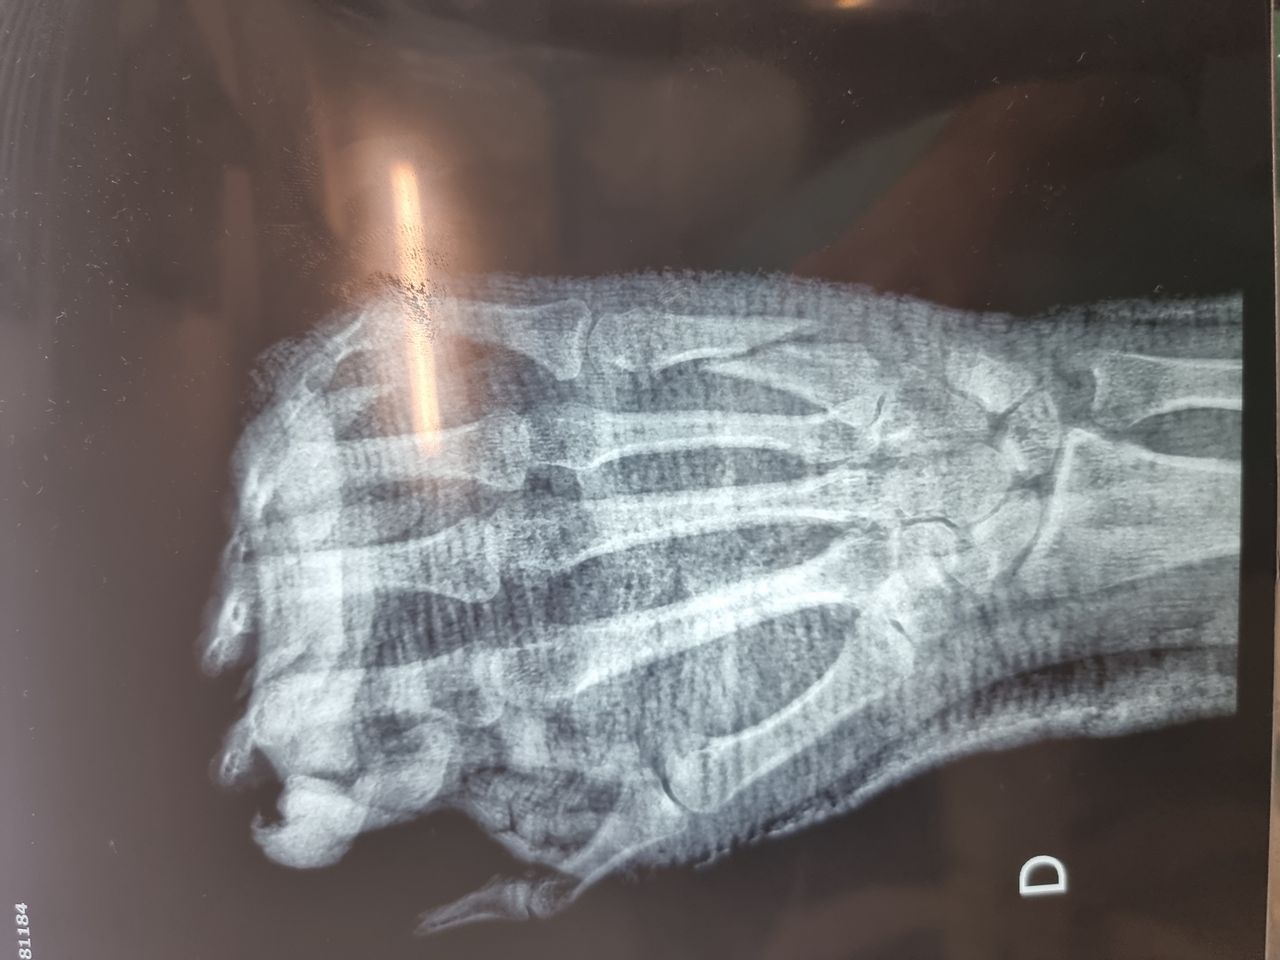

-ESCAFÓIDE: Tratamento da Fratura e da Pseudo-artrose do Escafóide com ou sem DISI e outras complicações, bem como Lesões Ligamentares da Mão e Punho, incluindo as do Ligamento Escafo-lunar do Carpo. Bennett, Rolando, Barton, Monteggia, Galleazzi e outras fraturas especiais ou comuns.

-FRATURAS: do antebraço, punho, metacarpos e  falanges.